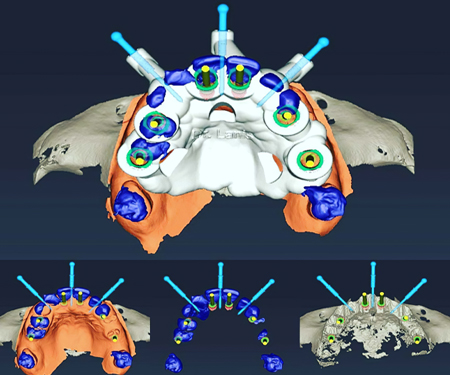

打印-树脂